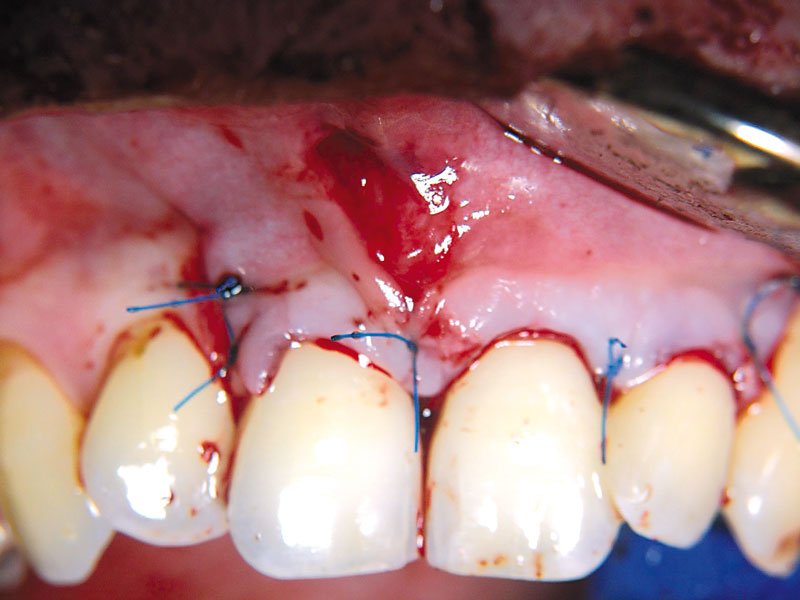

09/11 - Flap closure.Non-contained intrabony defect treated using cerabone®, collprotect® membrane and Straumann® Emdogain® - Dr. T. Schwaar (2)